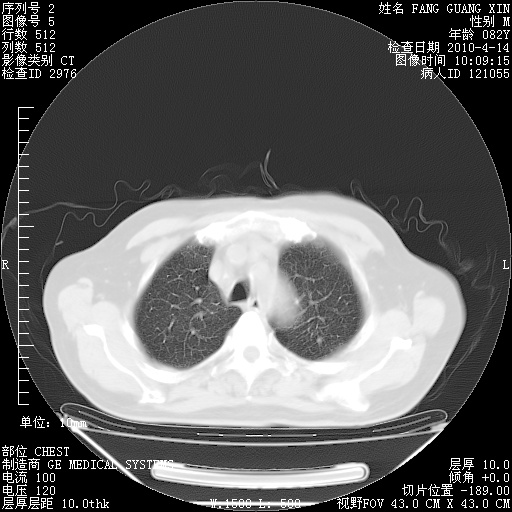

肺部CT平扫未见异常。